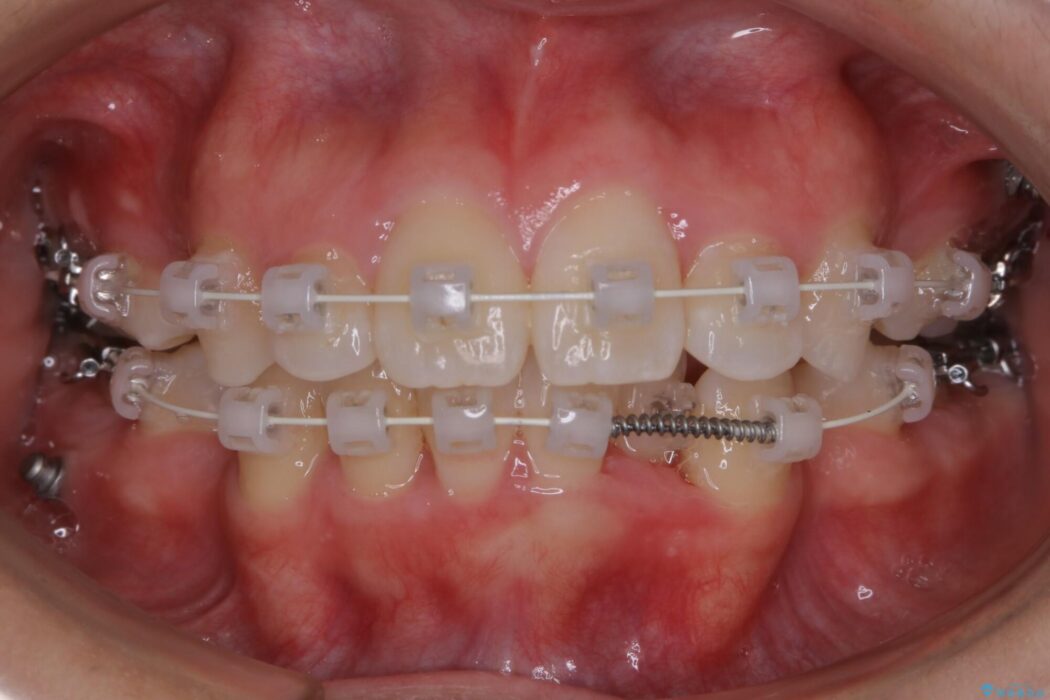

よって本症例では抜歯により歯の本数を減らすことにより整えるスペースを確保してワイヤー装置にて歯列矯正を行うこととしました。

本症例の患者様は顎の骨が小さく歯をきれいに並べるための隙間がないため、歯が重なったり傾斜してしまっていました。

抜歯を行うことによりスペースを確保し、小さい骨幅でも歯並びを整えることができます。